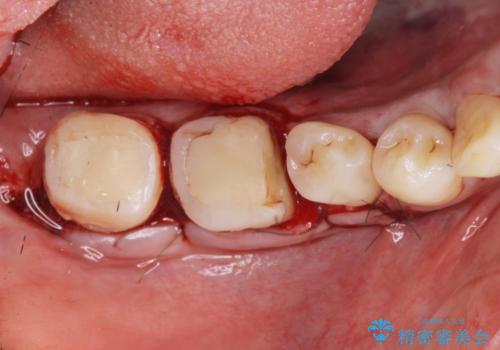

奥歯は既に根管治療が為されクラウンを装着する必要性がある状態ですが、歯の高さが低くクラウンの安定性・強度を担保するために歯周外科を行う治療計画としました。

歯周外科を行うことで、歯ぐきの位置を下げ歯の高さを作り出し安定したクラウンの装着が可能となります。また同時に舌の邪魔となっていた骨隆起の除去を行うこととしました。